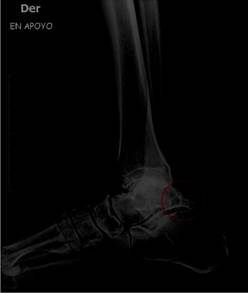

Figura 2 Imagen radiográfica vista lateral de tobillo derecho en apoyo, paciente masculino de 77 años, presencia de Proceso de Stieda. (círculo rojo).